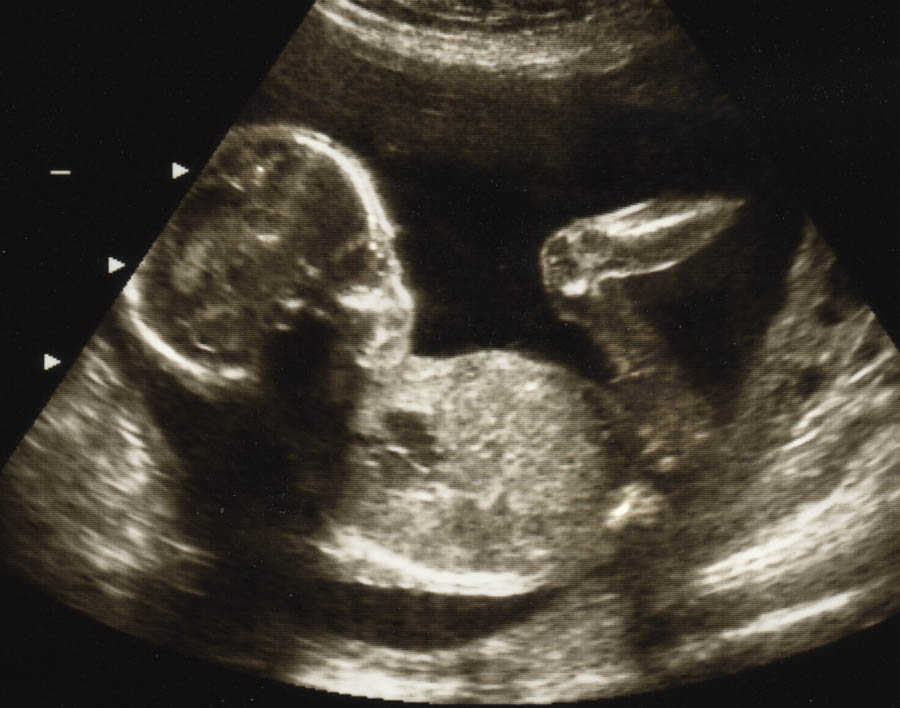

Both the state House and Senate measures would allow for abortions past 24 weeks, and up until the point of birth, in cases of a lethal fetal anomaly.